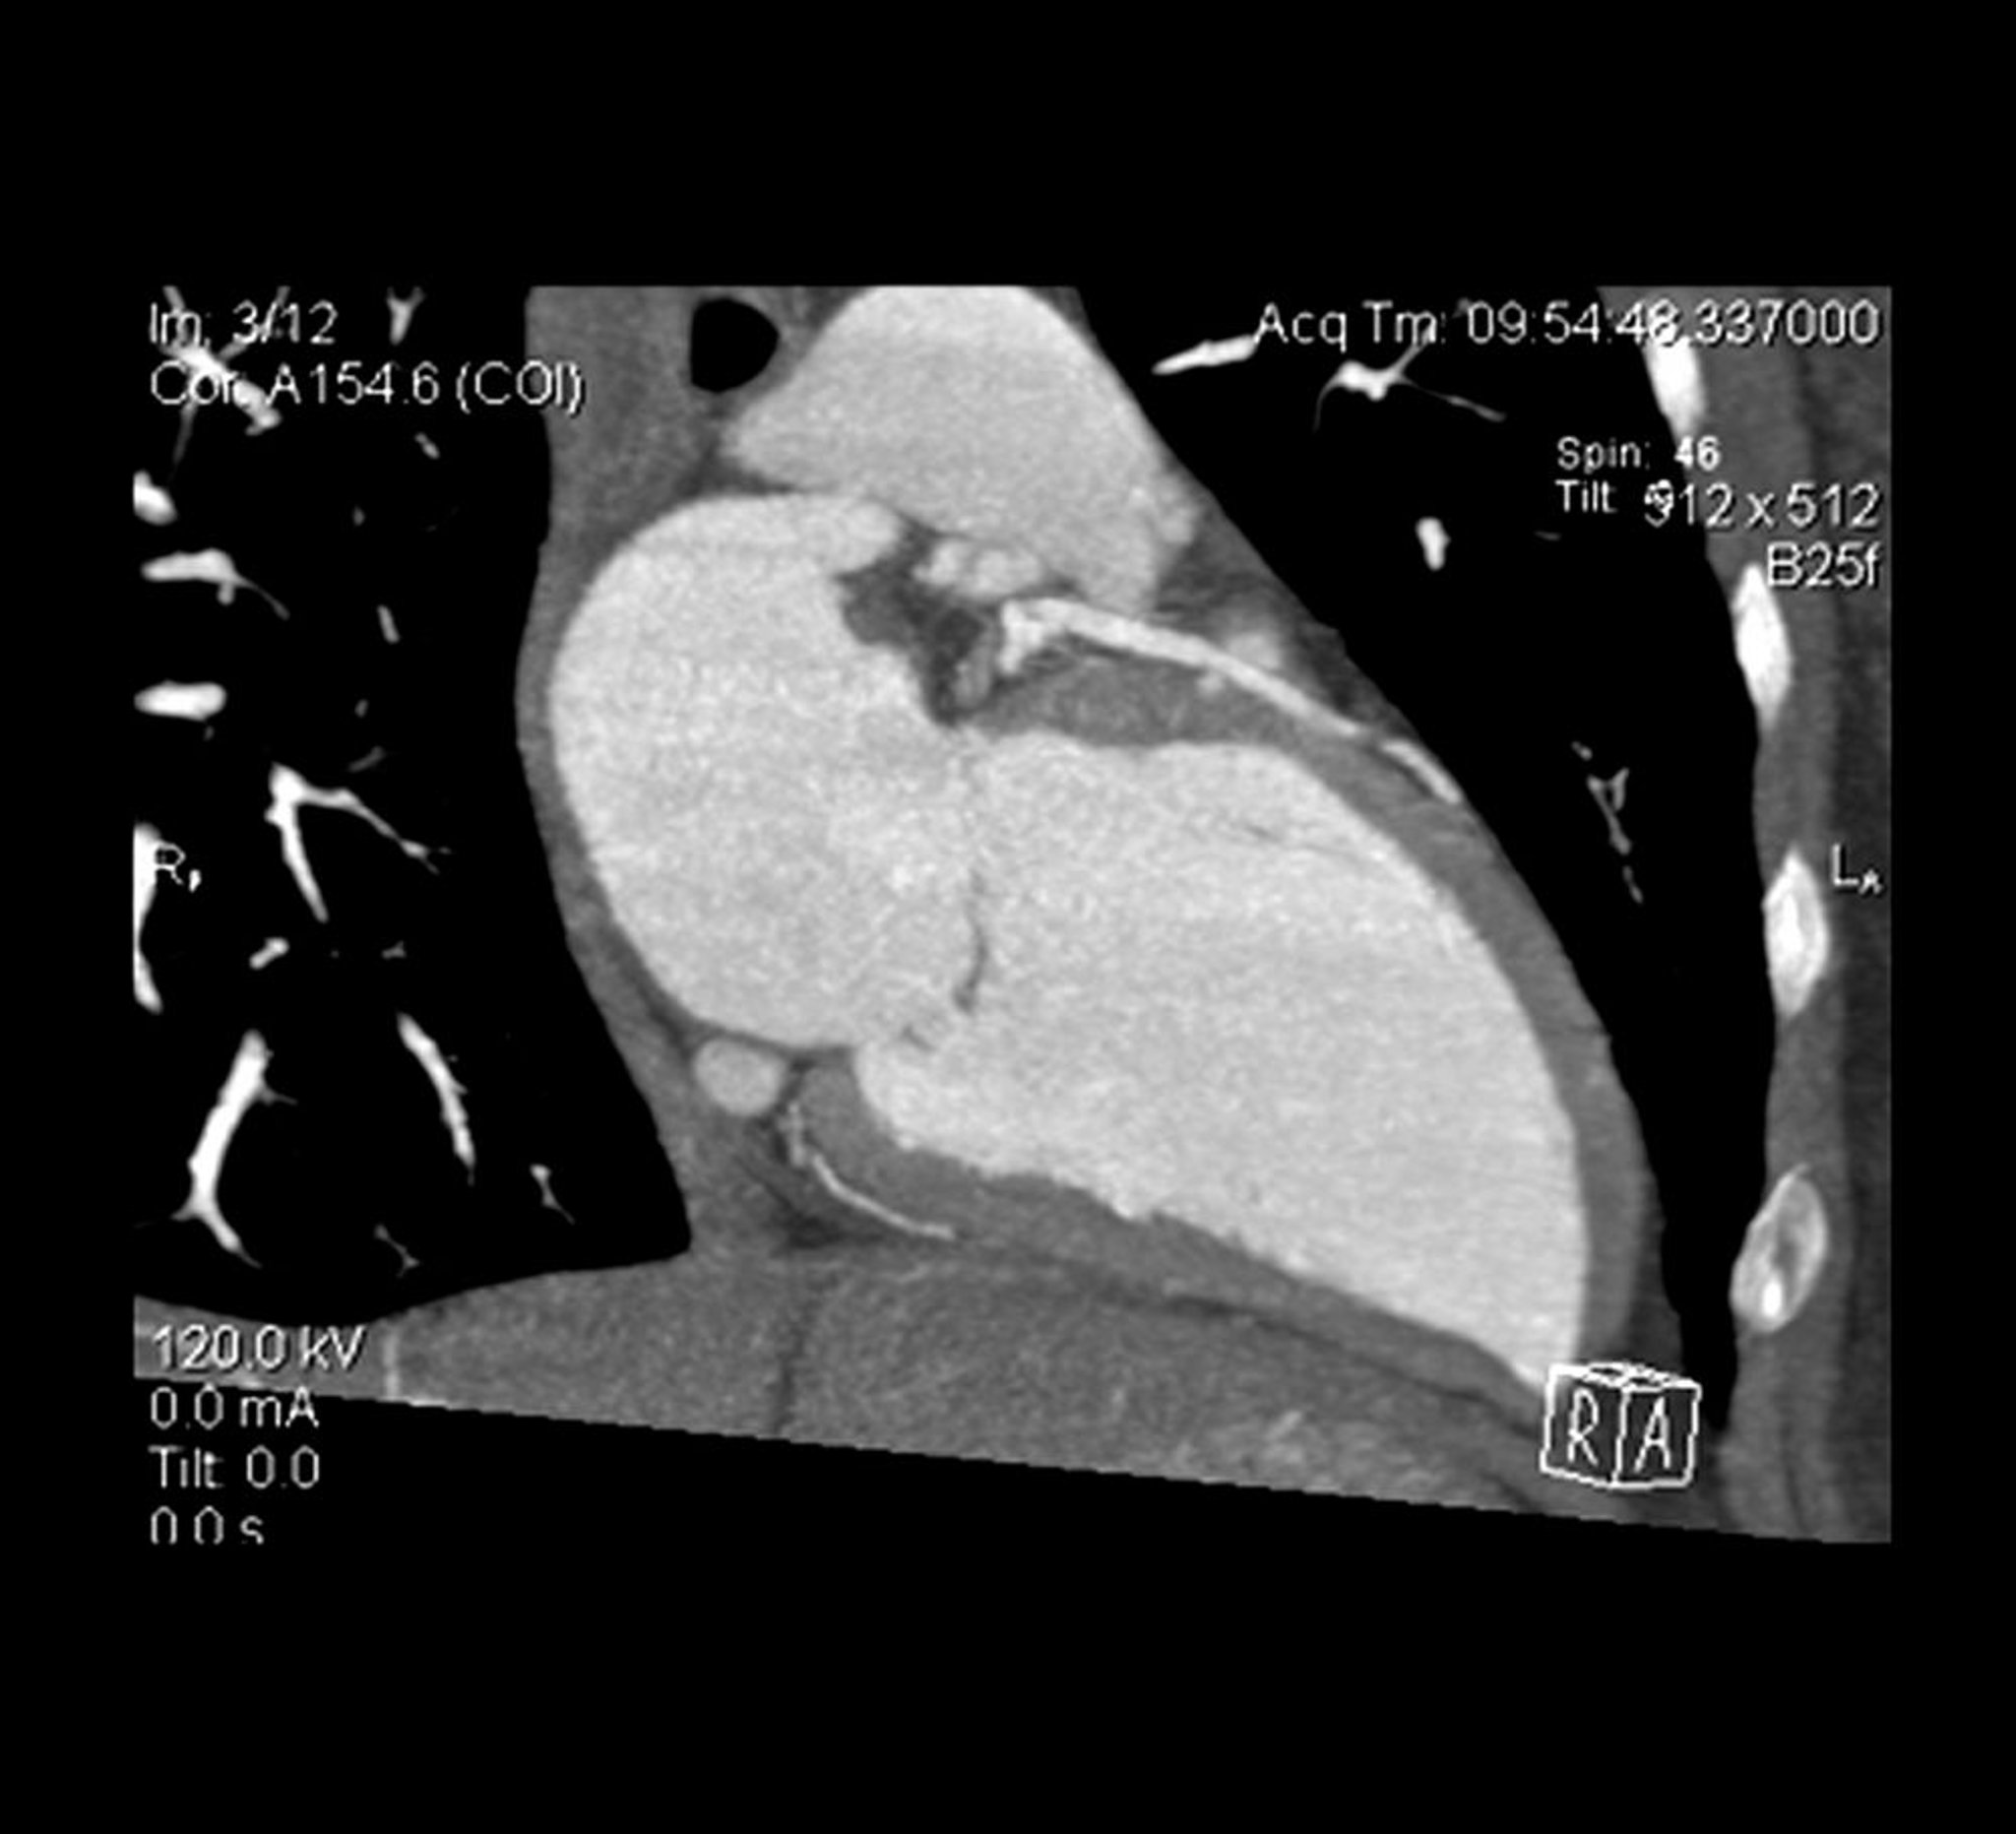

心血管造影CT

心血管造影CTの断層像に左室および左前下行枝が写っている。